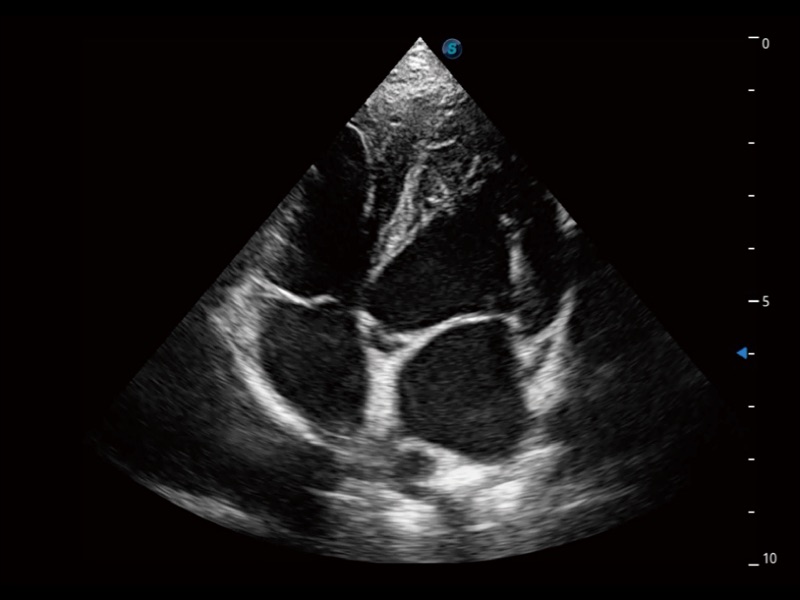

通過(guò)360度任意調(diào)節(jié)3條M型取樣線(xiàn),在同一心動(dòng)周期上觀(guān)察心臟不同位置的運(yùn)動(dòng)曲線(xiàn),得到準(zhǔn)確的心功能測(cè)量數(shù)據(jù),有效評(píng)估心肌運(yùn)動(dòng)及左心室功能。

實(shí)時(shí)用顏色表示心肌組織運(yùn)動(dòng),觀(guān)察和定量組織的運(yùn)動(dòng)情況,對(duì)快速檢測(cè)與評(píng)估心肌的灌注和活性、電傳導(dǎo)及心肌收縮和舒張功能等均能提供重要的診斷信息。